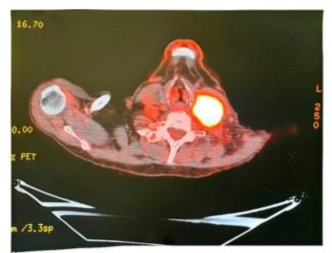

Whole body PET/CT scan was done and showed FDG avid 6.4x4.0 cm left level 3/4 cervical mass, SUV 18.5, with no suspicious FDG uptake elsewhere (Figure 4).

Figure 4: PET/CT scan was done and showed FDG avid 6.4x4.0 cm left level 3/4 cervical mass, SUV 18.5.